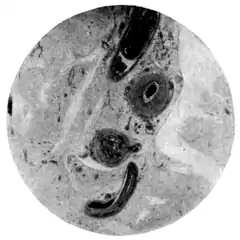

Fig. 132.—Schistosomum hæmatobium miracidium. (After Looss.)

The free larva (Fig. 132).—In newly voided urine the ovum

presents a somewhat brownish appearance, and generally contains a ciliated larva (miracidium). After a time the larva may escape through a longitudinal rupture in the shell. It then swims about, but, unless supplied with fresh water, soon perishes. If the urine be freely diluted with water, the larva not only escapes more quickly from the shell but also continues to live, swimming and gyrating very actively, for a considerable time. While swimming, the body of the little animal undergoes many changes of shape. For the most part, when advancing, it is oblong, tapering somewhat posteriorly; when more stationary it tends to assume a spherical form. It moves by means of the cilia which, with the exception of the minute papillary beak, thickly cover the entire body. On carefully examining the larva, a canal may be traced from the beak into what looks like a rudimentary stomach; on both sides of this, two much smaller gland-like organs can be seen, from each of which a delicate tube passes forwards and opens, apparently, somewhere in the neighbourhood of the beak.